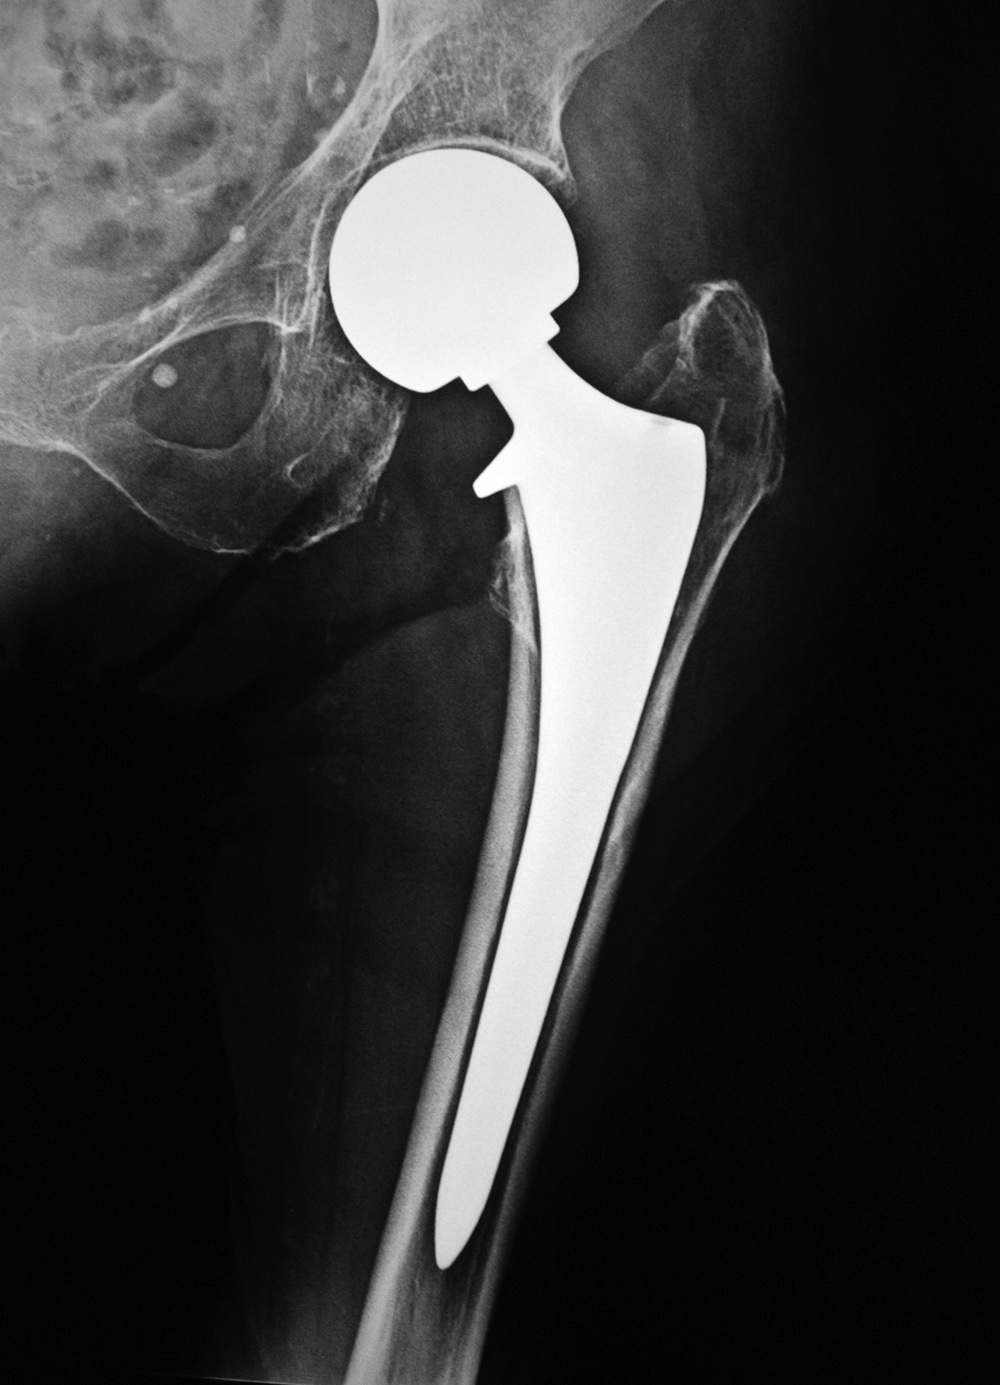

Modular non-cemented total hip prosthesis (THA) |

Implants consist of a proximally porous coated stem and prosthetic head and a porous coated metal acetabular component with a polyethylene liner. From Benjamin, 1994 |